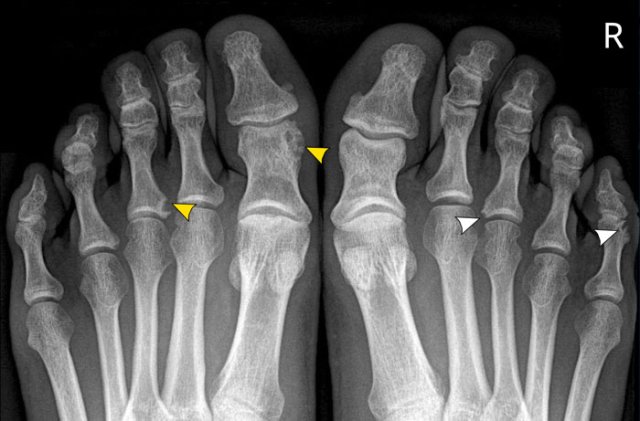

This patient suffered from an episode of campylobacter gastroenteritis.

After a few weeks clinical symptoms of arthritis emerged.

Image

On the right there are erosions at the base of the 3rd proximal phalanx and at the head of the 5th proximal phalanx (white arrowheads).

On the left there is an erosion at the base of the 3rd proximal phalanx and lytic changes of the head of the 1st proximal phalanx (yellow arrowheads).

Based on the aspecific imaging findings alone, it is difficult to diagnose reactive arthritis.

The preceding infection makes it more likely.